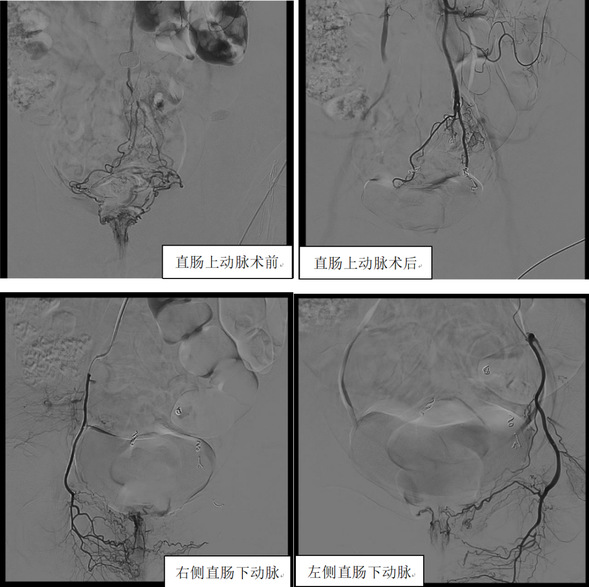

手术选取远桡动脉入路

术中部分图像

次日,患者激动的对莫庆国说,“真是太厉害了,今早排便一点血都没有了,手上也没有明显的手术切口,整个治疗过程简直太舒服了。”